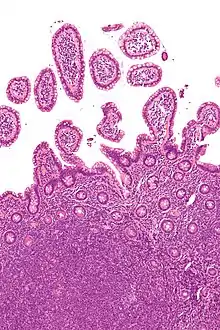

| Micrograph showing mantle cell lymphoma (bottom of image) in a biopsy of the terminal ileum. H&E stain. | |

The history and physical examination may reveal some of the signs and symptoms consistent with Mantle Cell Lymphoma. Biopsy of the involved tissues (such as the lymph nodes, bone marrow, gastrointestinal tract, spleen or other areas) shows the characteristic histopathologic changes of MCL. There are distinct growth patterns of MCL seen on biopsy; these include the diffuse type, nodular type, mantle zone lymphoma and in situ mantle cell lymphoma.[7] In the diffuse growth pattern, there is a diffuse growth of lymphoma cells throughout the lymph node resulting in effacement of the architecture of the lymph node.[7] In the nodular type, there are large nodules of MCL cells in the lymph node with no germinal centers observed.[7] In MCL with expansion of the mantle zone, the lymphoma cells cause expansion of the mantle zone around normal germinal centers.[7] And in MCL in situ, the lymphoma cells are contained within the mantle zone without expansion.[7] Histologically, the lymphoma cells in classic MCL are characterized as small to medium lymphocytes with scant cytoplasm and clumped chromatin with prominent nuclear clefts and the nucleoli are not visible.[7] There are cytologic subtypes; the blastoid subtype, is characterized by round nuclei, fine chromatin with some distinct nucleoli.[7] The pleomorphic subtype is characterized by nuclei that vary in size and shape with some having a cleaved form.[7] The blastoid and pleomorphic subtypes of MCL are associated with a more aggressive course.[7]